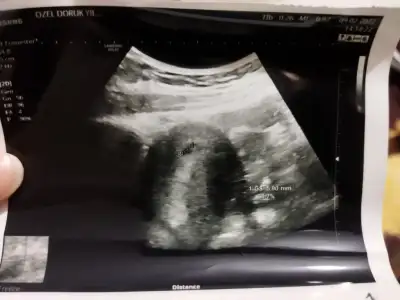

Karından ilki bir aylık diğeri üç yâda iki

• IMG_20220519_212918.webp

IMG_20220519_212918.webp

27,3 KB · Görüntüleme: 73